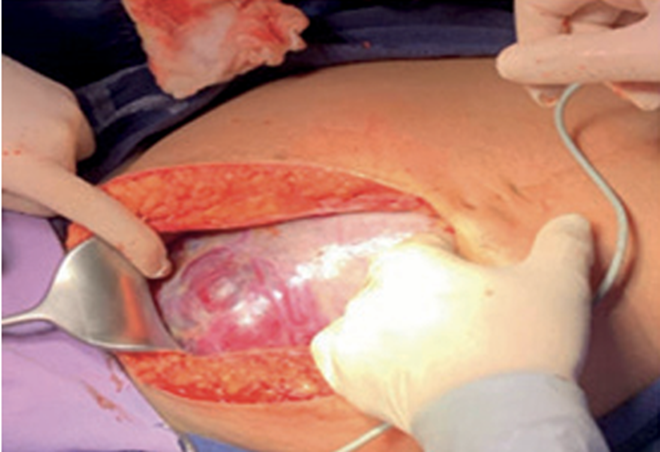

Se realizó una incisión mediana supra e infraumbilical y una vez en cavidad abdominal se evidenció macroscópicamente el área de infiltración placentaria sobre el segmento uterino evadiendo el útero e infiltrando la vejiga (figura 5).

Se realizó ecografía intraoperatoria para evitar la incisión transplacentaria, decidiendo realizar una histerectomía a nivel del fondo uterino. La extracción fetal fue en podálica y se realizó ligadura oportuna del cordón umbilical, que se abandonó intraútero en conjunto con la placenta al realizar la histerorrafia.